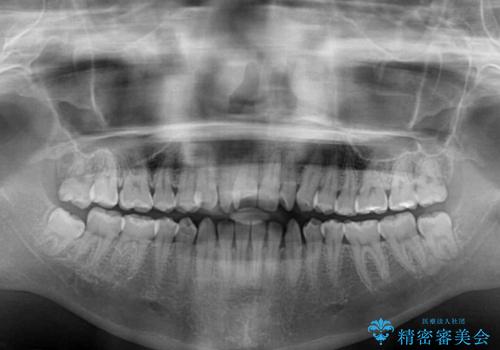

- 前歯のデコボコと、下顎の変位と受け口を気にして来院された患者様です。

初診時には大学病院にて顎の骨を切る外科矯正を勧めましたが、妥協的なゴールでも構わないので外科処置をせずに矯正を行いたいとのことでした。

まずは急速拡大装置にて上顎骨を側方に拡大し、インビザラインにて歯列と咬合を整えることとしました。

上顎骨を拡大したことで、下顎の歯列を上顎が受け入れられるようになりましたが、インビザラインでは咬み合わせを改善させることができなかったため、ワイヤー矯正にて仕上げることとしました。

ワイヤーを使用したものの、上下前歯のオープンバイトがなかなか改善されませんでしたが、患者希望により治療終了となりました。